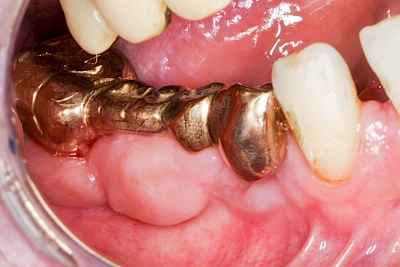

Diese Vermehrung von Bindegewebe in einem frei gewordenen Raum ist eine Sonderform der Anpassungsreaktion menschlicher Zellen und wird als Vakatwucherung bezeichnet.

Früher wurden im Unterkiefer mitunter Brücken zum Ersatz fehlender Zähne als sogenannte "Schwebebrücken" gestaltet. Die Idee dabei war, dass man die Brücke insgesamt besser reinigen kann. Allerdings war das für die Patienten mitunter irritierend für die Zunge und vor allem beim Essen gewöhnungsbedürftig. Teilweise haben sich hier reaktiv Vakatwucherungen der Kieferkammschleimhaut gebildet und den Raum unter der Brücke wieder verschlossen.